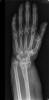

Carpo normal